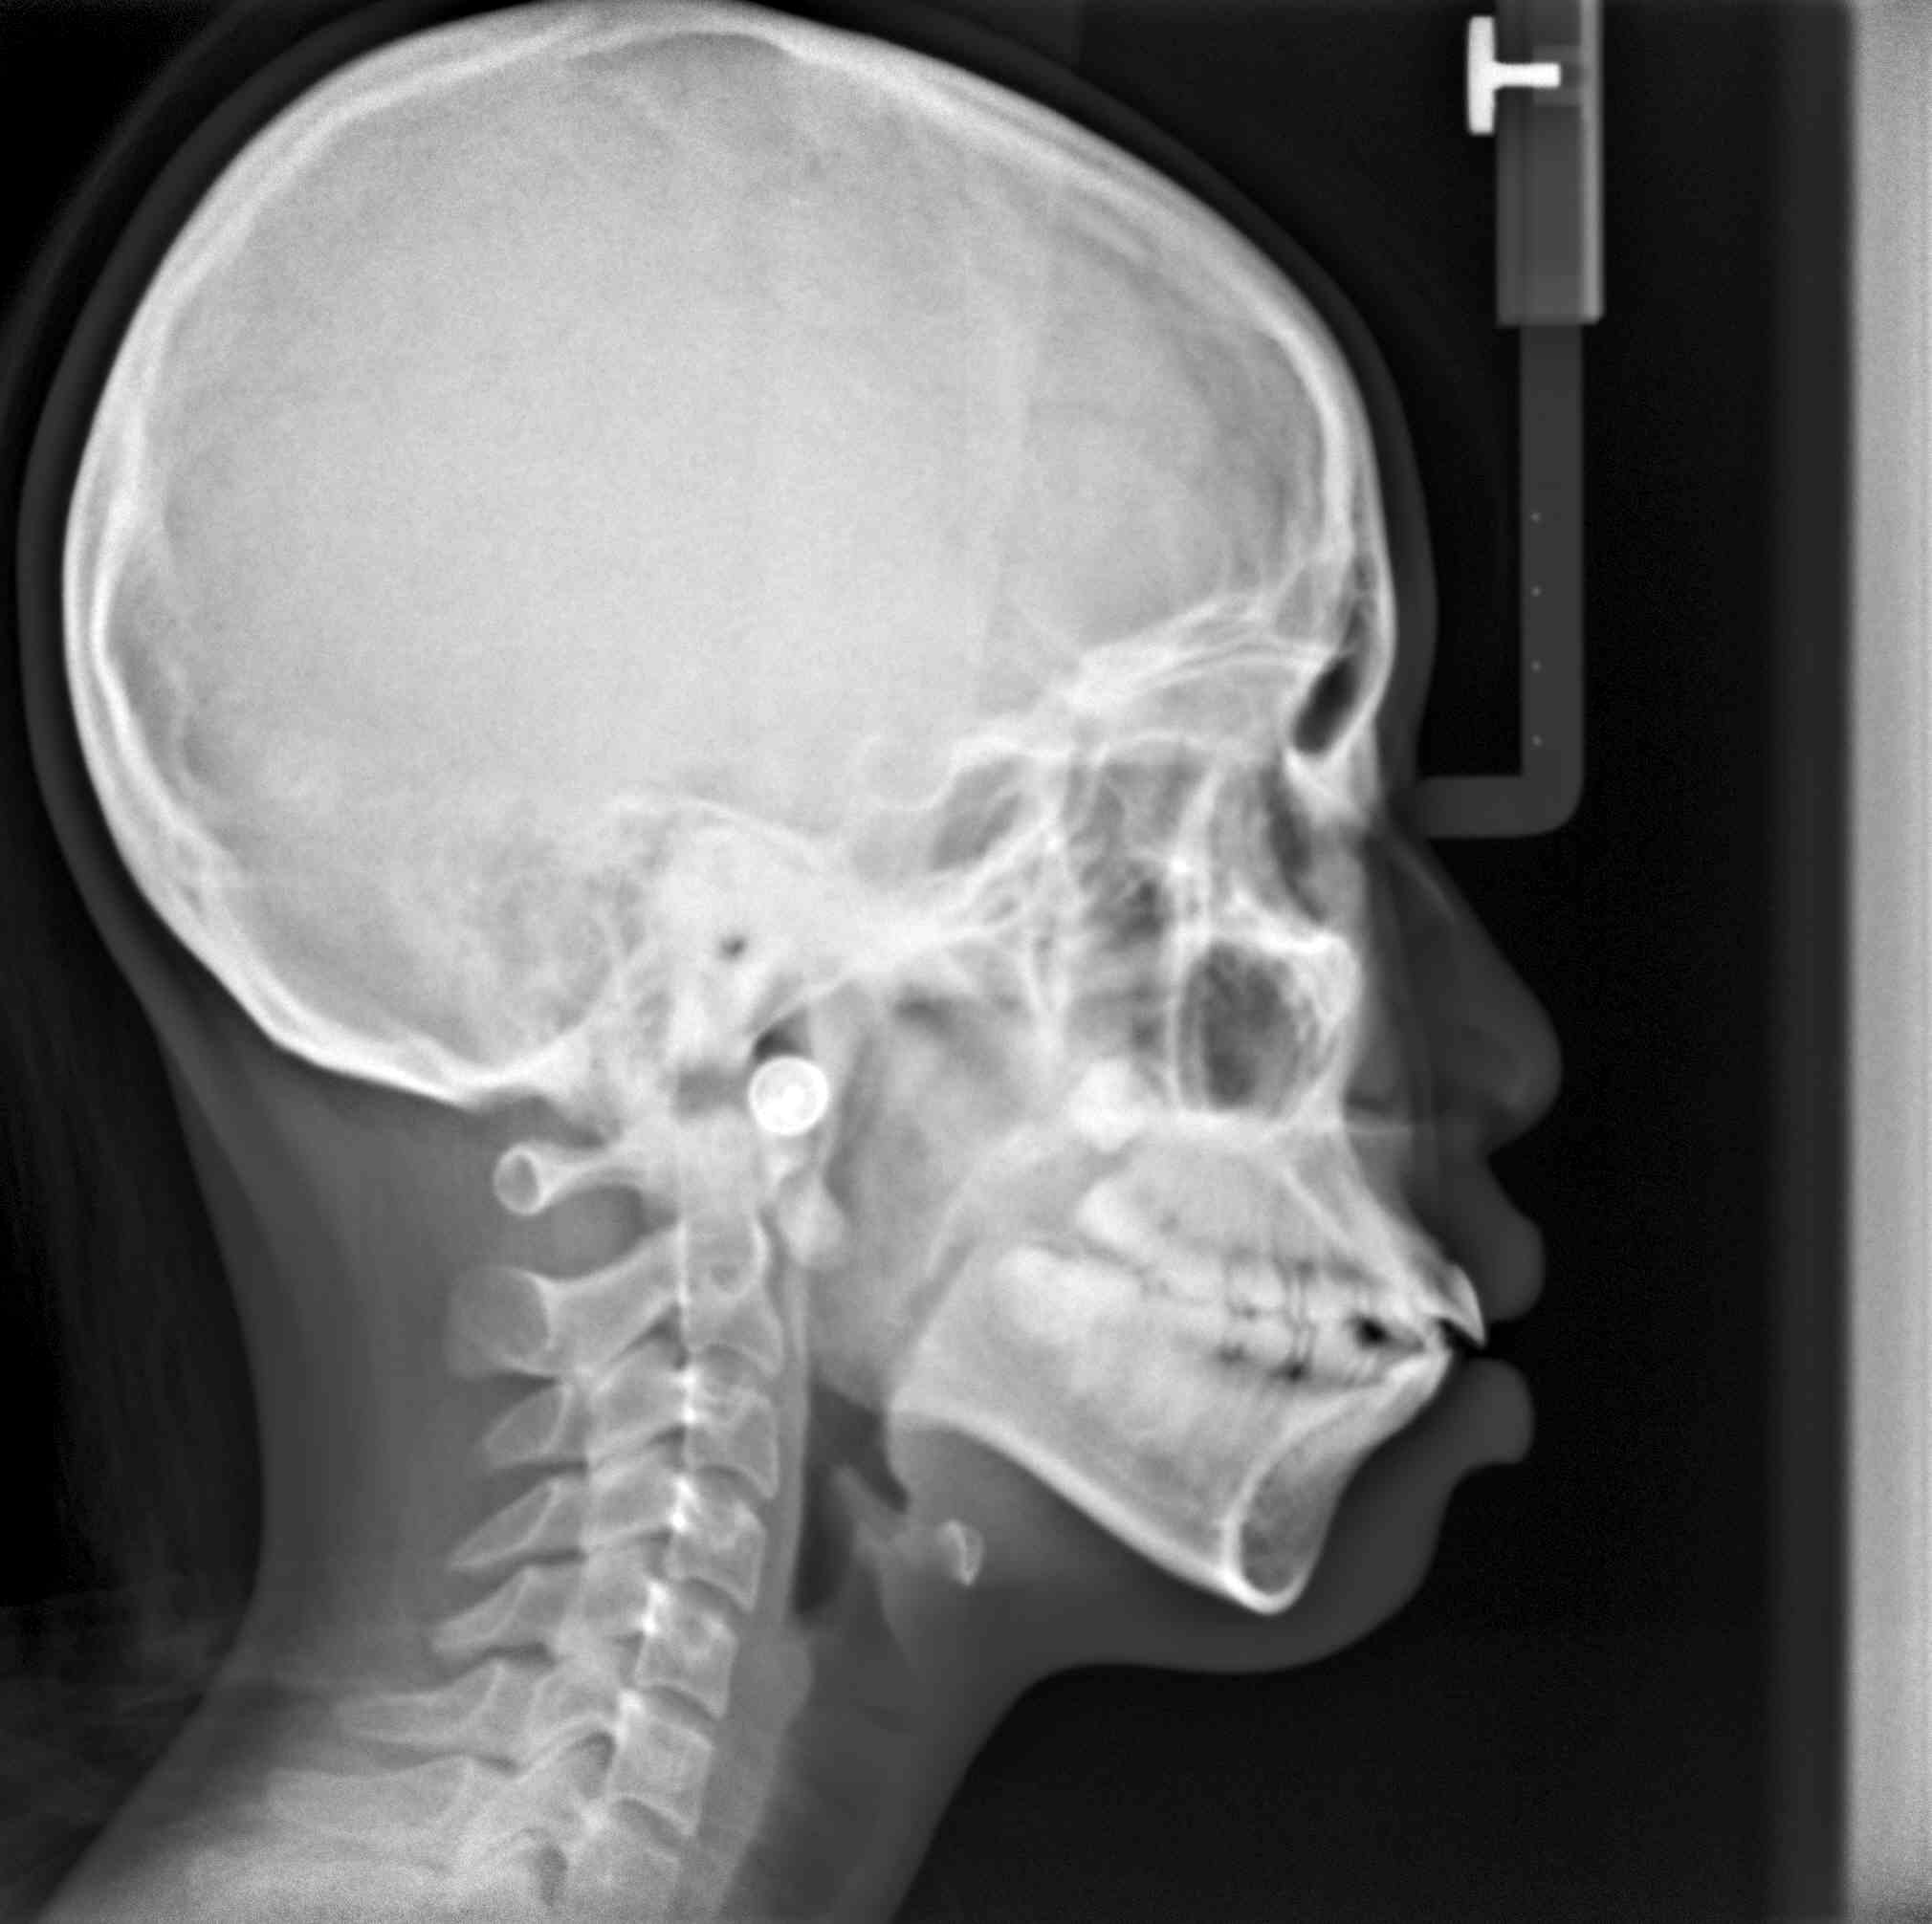

拔牙案例 首頁 案例分享 齒顎矯正 拔牙案例 - 拔牙案例 - 年紀:15歲 矯正方式:隱適美隱形矯正 時間:30個月 主訴:暴牙、笑起來不好看、咬合不正 矯正前 矯正後 矯正前 矯正後 矯正前 矯正後 聲明:本所療程皆由專業醫生評估後,依照個人口腔狀況進行治療。因每位患者個別狀況不同,術後狀況也不盡相同,需親來本所由醫生評估。